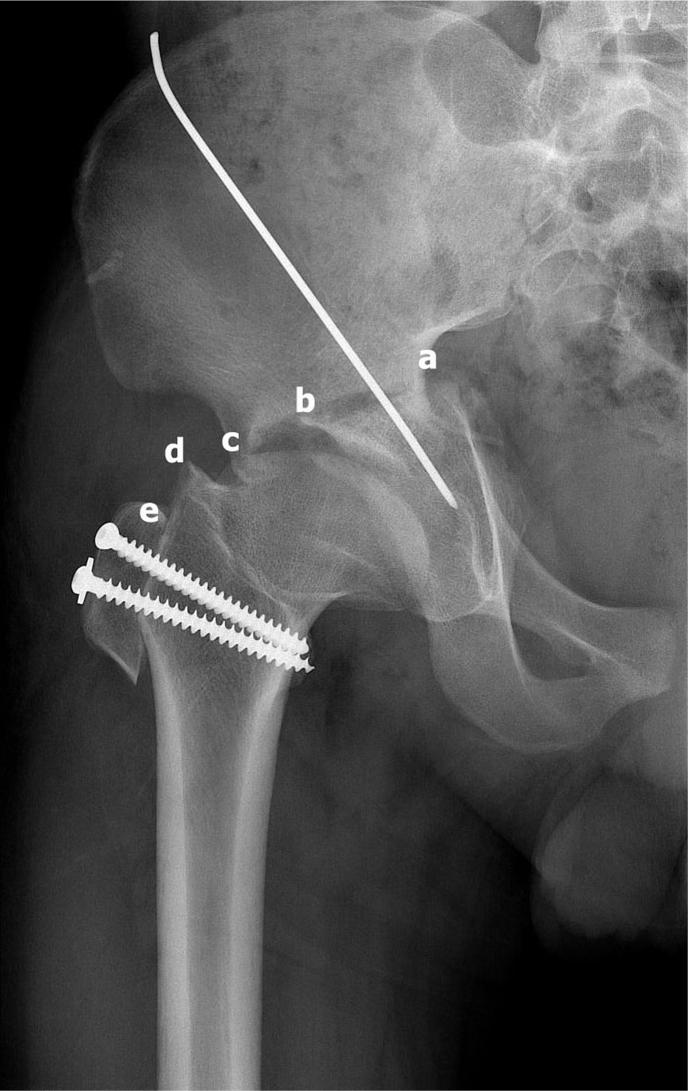

Disparity in size between femoral head and acetabulum could promote premature degeneration of the hip joint. The purpose of this study was to report the results of Kawamura's dome osteotomy for acetabular dysplasia due to sequelae of Perthes' disease.

Fourteen patients (14 hips) operated between 1999 and 2012 were retrospectively reviewed. There were 9 males and 5 females with a mean age of 29 years (range, 15-54 years). Functional and radiological results were reviewed at mean follow-up of 9 years (range, 4-12 years).

Pain relief was obtained in 13 of 14 (92.8%) patients postoperatively. Good to excellent functional outcome was obtained in 10 of 14 (71.4%) patients. Mean Harris hip score was improved from 63 to 84 (p < 0.05) at the final follow-up. Improvement of limping gait was observed in 10 of 14 (71.4%) patients. Center edge angle improved from mean 24° (11-36°) preoperatively to mean 35° (27-46°) postoperatively (p < 0.05), acetabular angle improved from mean 43° (36-49°) preoperatively to mean 37° (32-44°) postoperatively (p < 0.05), acetabular head index improved from mean 69% (50-83%) preoperatively to mean 85% (73-100%) postoperatively (p < 0.05). Progression of arthrosis stage occurred in 3 of 14 (21%) patients. None of the hip with preoperative Stulberg III, 2 of 9 hips with Stulberg IV and 2 of 2 hips with Stulberg V needed conversion to total hip arthroplasty during the follow-up.

Dome osteotomy of the pelvis combined with trochanteric advancement could give a reasonable treatment outcome for acetabular dysplasia due to Perthes' disease at mid to long-term follow-up. Advanced stage of arthrosis, preoperative Stulberg V and no improvement of limping gait after the surgery possibly associated with poor outcome.